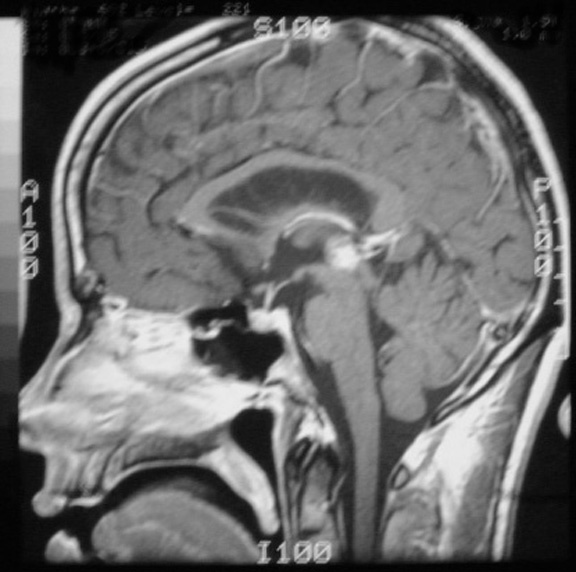

T1+Gad sagittal demonstrating enhancing pineal germinoma